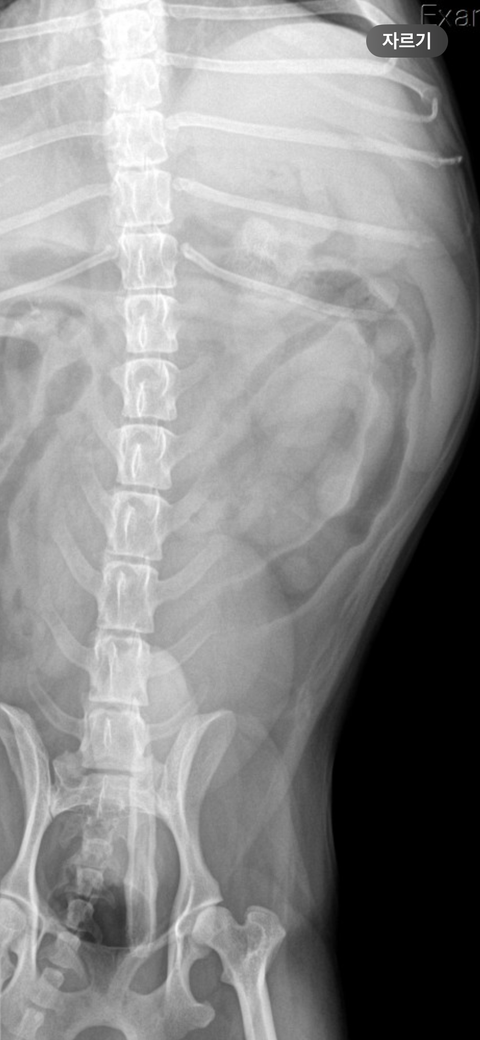

엄마가 2일 전과 1일 전에 시츄에게 족발을 주어서 2일 전부터 간헐적으로 토하다가 금일 새벽에 12번 정도 토를 하고 2cm 정도 되는 뼈를 토했습니다. 그리고 변도 조금씩 묽게 싸고 금일 새벽에 뼈를 포함한 저런 똥을 쌌습니다. 사진에 보시다시피 피가 살짝 섞여있습니다. 그래서 병원을 방문하였더니 위에 뼈가 있는 것이 아니라 소장에 가로 2.7cm 세로 2cm 정도의 뼈가 들어있는 거 같다고 판단하셨습니다. 강아지가 11살이라 나이도 있고 디스크로 인해 스테로이드를 3주 정도 복용하여 간수치가 좋지 않다고 하여 수술을 해야 할지 고민이 된다고 하시고 당장 수술을 결정하자니 뼈가 그리 크지 않아 위에 사진처럼 나올 수도 있을 거 같다 보호자 의견에 따르겠다고 말씀하셨습니다. 수술을 결정하지 않는 판단을 보호자가 하신다면 오늘 5시간 정도 수액을 맞고 엑스레이를 다시 찍어본 후 뼈가 좀 내려갔는지 확인을 해보면서 지켜보는 방향으로 가자고 하셨습니다. 하지만 금일은 금식 금수이지만 내일 밥을 주고 물을 줬을 때 토하게 된다면 병원에 방문하여 수술을 고려하자고 하셨습니다. 수의사 선생님들의 의견을 듣고 싶습니다..

주치의의 판단이 옳은 부분이 많지만, 통상 구토를 12번이나 할정도로 이물 폐색 가능성이 높으면서 방사선 사진에서 폐색부가 저런 양상으로 보인다면 바로 배를 여는게 교과서적인 추천사항입니다.

폐색이 유지되면 이차적인 췌장염과 장괴사가 가능하여 환자를 잃을 수 있으니 방사선 사진을 다시 촬영하시고 이물이 관찰된다면 바로 배를 여는것을 추천합니다.